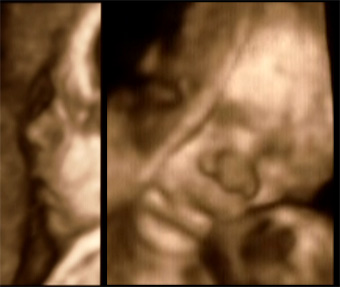

Deze week hebben we een pret echo laten maken van de kleine pruts in mama’s buik. Nadat de mevrouw alles gecontroleerd had en we zagen dat alles goed en gezond was, kon de pret beginnen. We konden een paar glimpen van zijn gezichtje opvangen, want meneer lag met zijn handen voor zijn gezicht in de placenta gedrukt. Niet echt een ideale houding voor mooie plaatjes, maar toch hebben we kunnen zien dat je op je grote broer gaat lijken. Zelfde mondje en neusje! Zie de beste plaatjes van pruts 2 hiernaast!